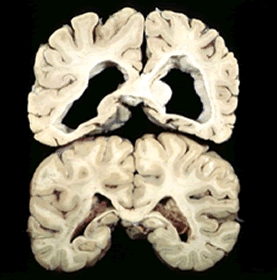

Malattia di Huntington: verso la comprensione degli interventi precoci

Malattia di Huntington-Immagine Credit Public Domain- La malattia di Huntington è la malattia neurodegenerativa più comune controllata da un singolo…